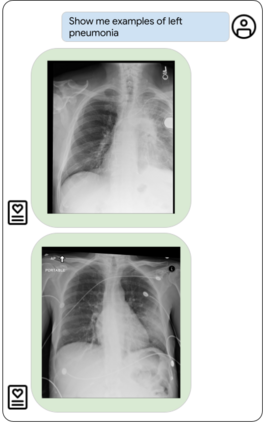

Our approach, which we call Embeddings for Language/Image-aligned X-Rays, or ELIXR, leverages a language-aligned image encoder combined or grafted onto a fixed LLM, PaLM 2, to perform a broad range of tasks. We train this lightweight adapter architecture using images paired with corresponding free-text radiology reports from the MIMIC-CXR dataset. ELIXR achieved state-of-the-art performance on zero-shot chest X-ray (CXR) classification (mean AUC of 0.850 across 13 findings), data-efficient CXR classification (mean AUCs of 0.893 and 0.898 across five findings (atelectasis, cardiomegaly, consolidation, pleural effusion, and pulmonary edema) for 1% (~2,200 images) and 10% (~22,000 images) training data), and semantic search (0.76 normalized discounted cumulative gain (NDCG) across nineteen queries, including perfect retrieval on twelve of them). Compared to existing data-efficient methods including supervised contrastive learning (SupCon), ELIXR required two orders of magnitude less data to reach similar performance. ELIXR also showed promise on CXR vision-language tasks, demonstrating overall accuracies of 58.7% and 62.5% on visual question answering and report quality assurance tasks, respectively. These results suggest that ELIXR is a robust and versatile approach to CXR AI.